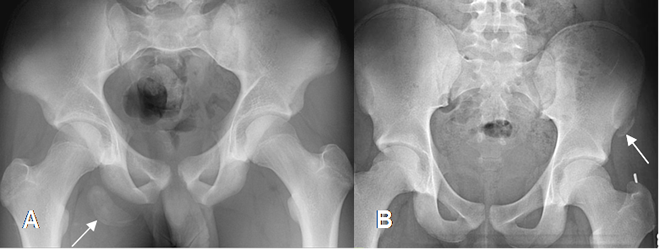

Las avulsiones son detectadas generalmente con Rx, pero puede necesitarse estudio comparativo o complemento con TAC y RM en algunos casos dudosos. (14). (Fig 77 y 78).

Fig 77. Avulsión.

A: Rx AP. Avulsión de la tuberosidad isquiática derecha.

B: Rx AP. Avulsión de la espina iliaca anterior superior izquierda.